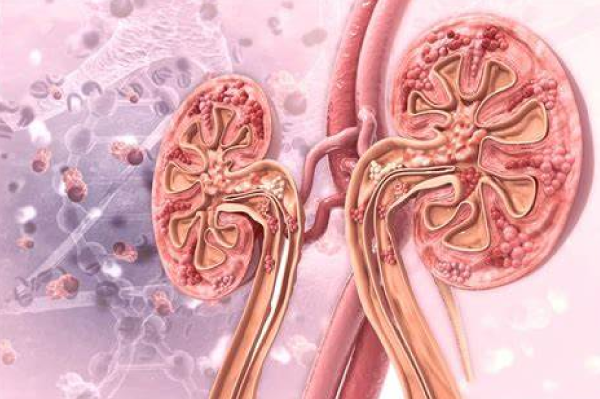

Stages Of Chronic Kidney Disease (CKD)

The experts and nephrologists have come up with the division of the various stages according to the level of filtration the kidney is still doing into five major stages in the order of the severity of the disease. All the stages are based and categorized according to the glomerular filtration rate or commonly known in medical terms as GFR.

The GFR of the body is affected by various factors apart from the serum creatinine levels, like the body size, sex, age, and even ethnicity of the person being tested.